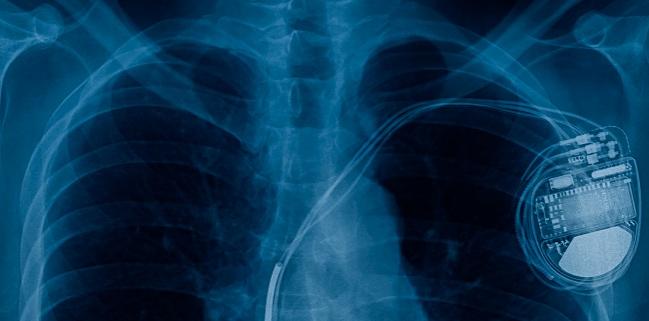

Worldwide, an estimated 10,000 to 15,000 leads from cardiac implantable electronic devices (CIEDs) are extracted each year, with device-related infection being the most common reason, according to the researchers.